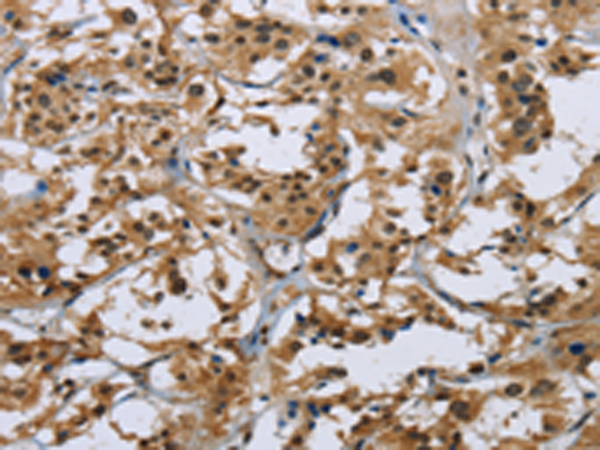

分类: 科研抗体货号: P11850别名: IL-31应用: WB,IHC反应种属: Human